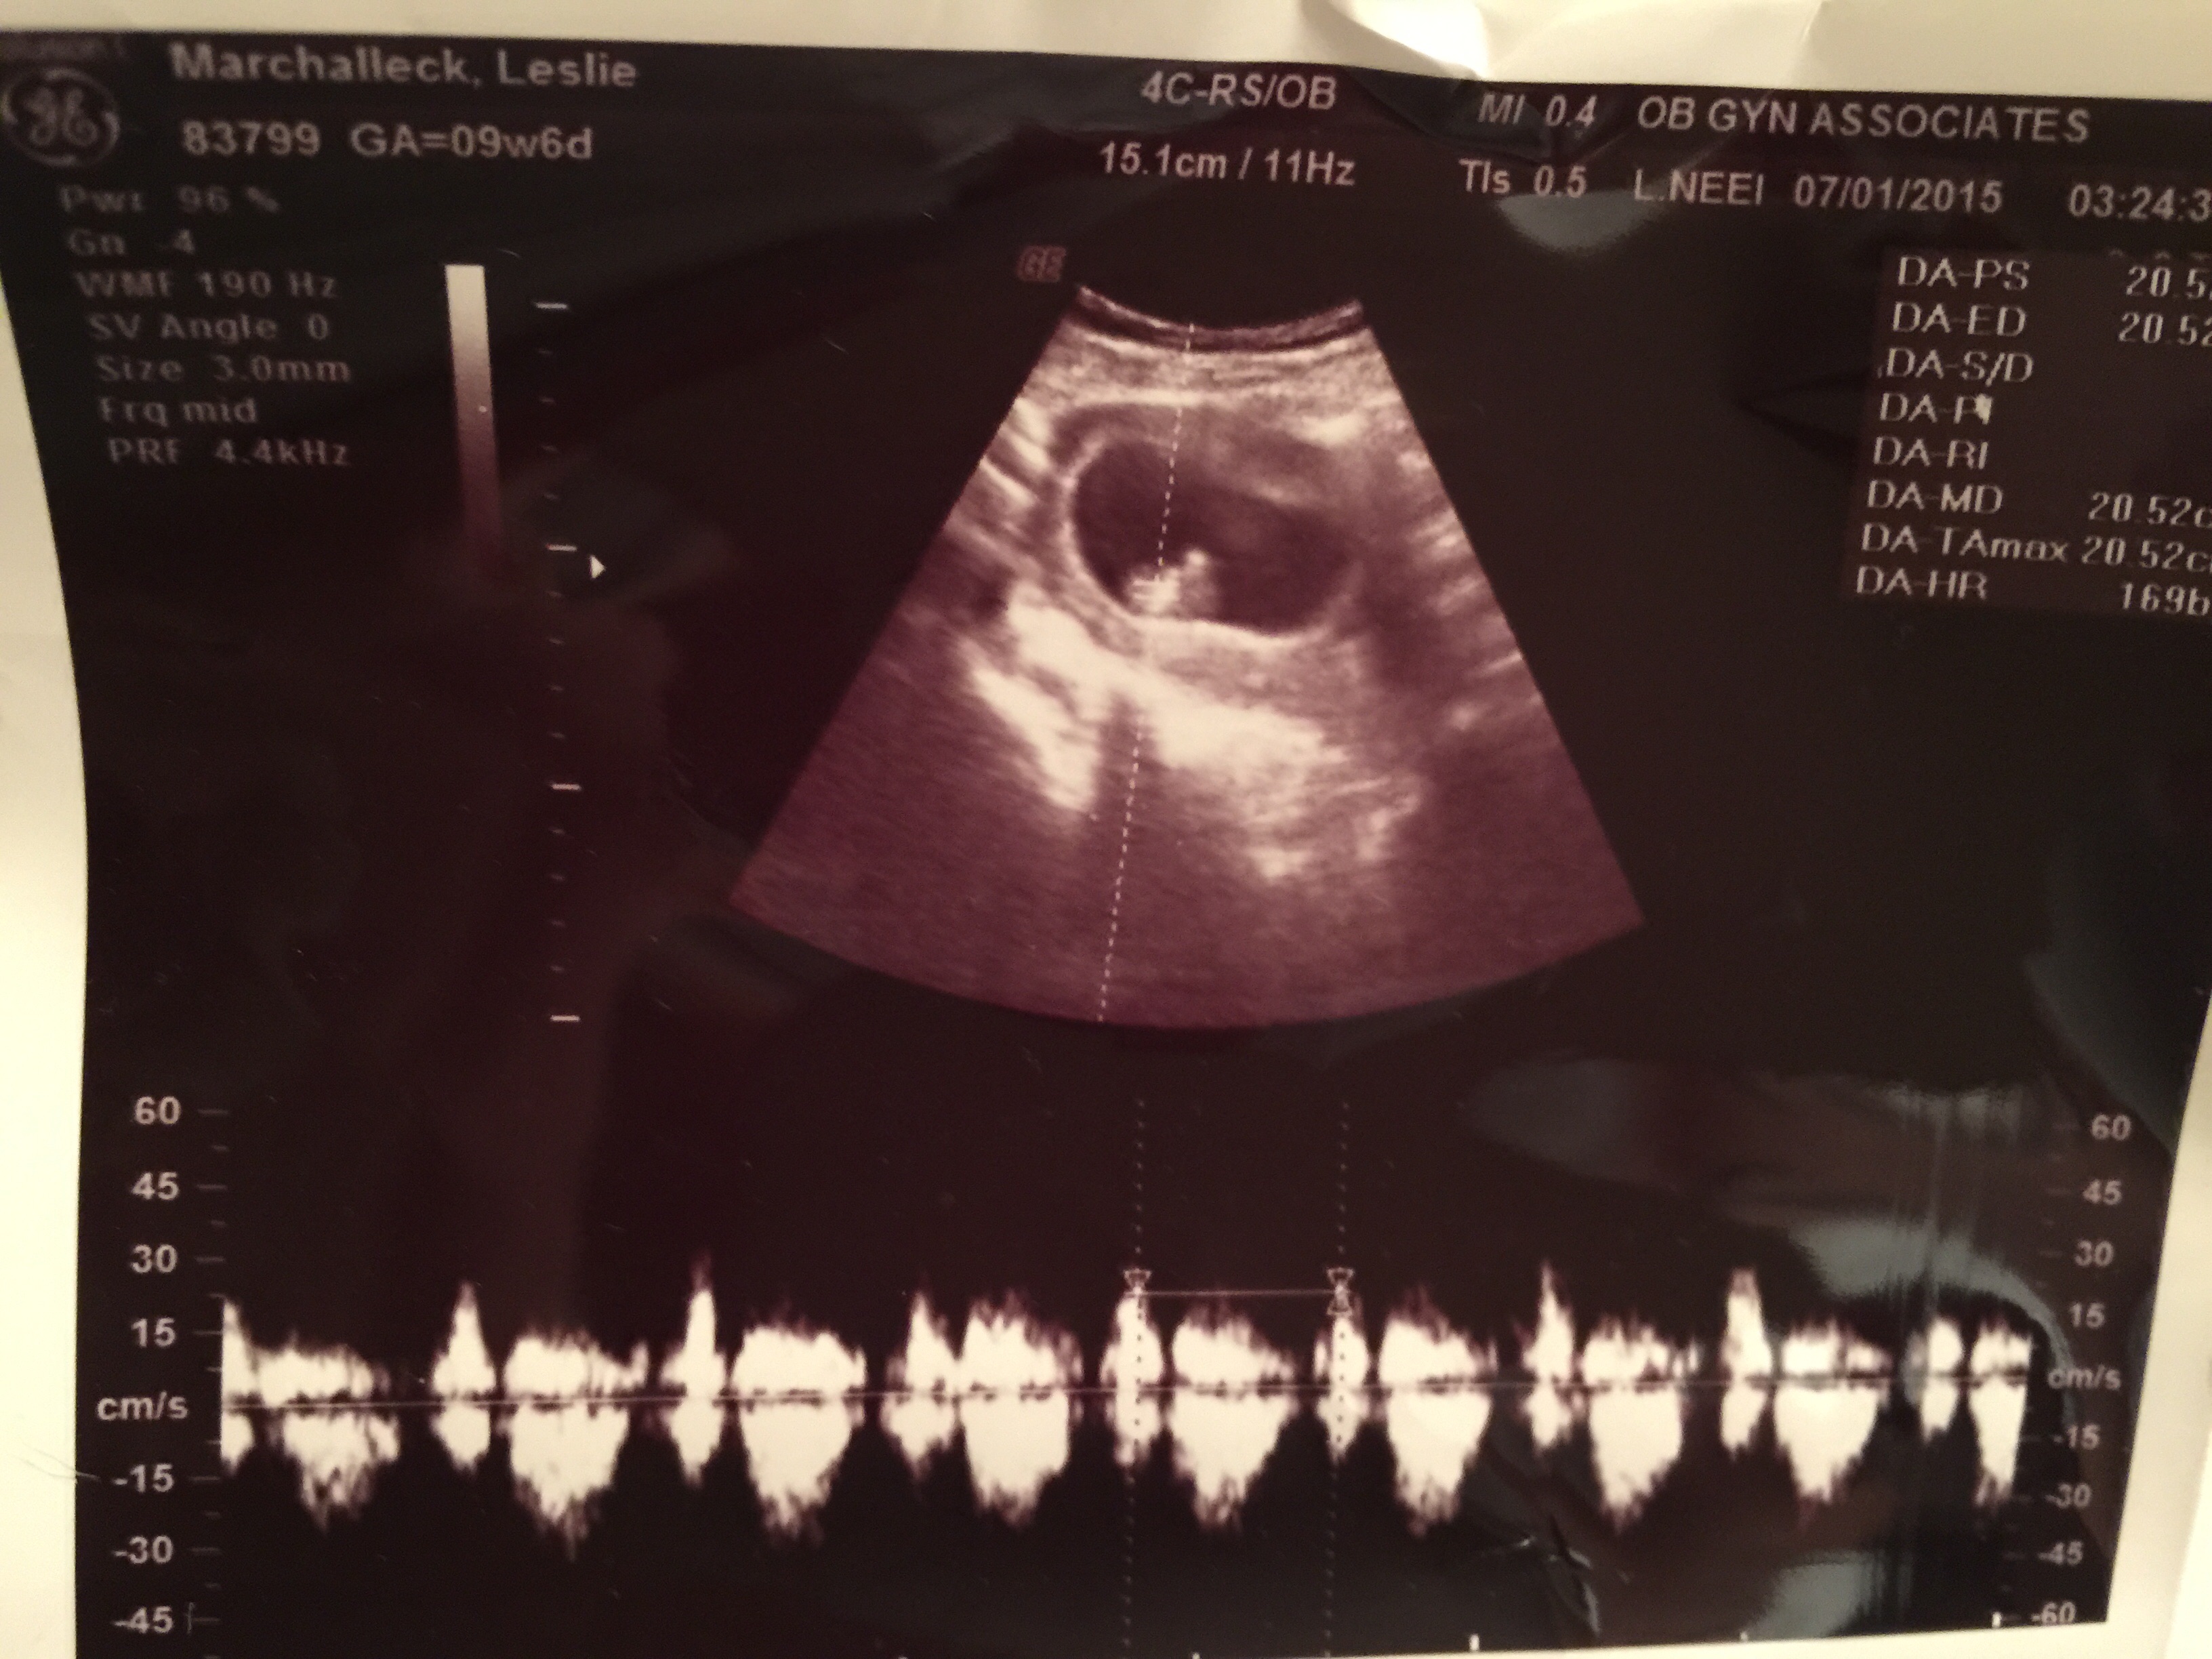

Got a great pic of our baby at 9w6d yesterday! Baby was verrrryy squirmy and was moving around. It was amazing to see baby active! Heart rate was 167 but she said that it was probably high because baby was moving so much! Due date February 24th.